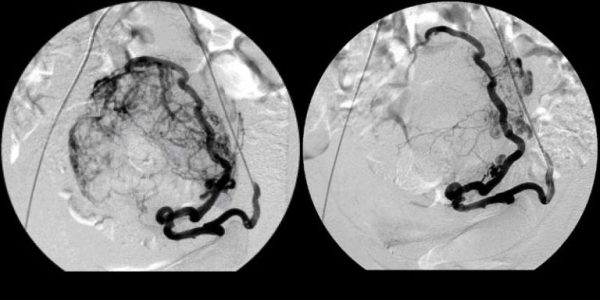

- артериовенозной мальформации (АВМ);

- аневризмах сосудов головного мозга.

- эмболизирующие спирали применяют при травматических повреждениях, аневризмах, артериовенозных мальформациях. Они подходят для сосудов с сильным кровотоком, так как вызывают немедленное тромбообразование. Изготавливают их из платины или нержавеющей стали. Спираль хорошо видна на рентгеновских снимках. Изогнутость катетера может деформировать спирали, и есть риск смещения спирали относительно первоначального положения;

- съемные баллоны используются при терапии АВМ и аневризмы. Этот баллон помещается в требуемый сосуд, затем заполняется через односторонний клапан физраствором. Ток крови в сосуде останавливается и эндотелий разрастается около баллона до полного зарастания сосуда. Иногда давление в баллоне превышает давление крови, и тогда баллон может лопнуть, а если давление в баллоне ниже, чем давление крови, – баллон может сжаться и передвинуться в другое место.